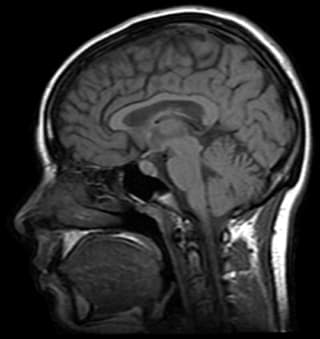

- CourseFreeFunctional Magnetic Resonance Imaging: Data Acquisition and AnalysisStarts: AnytimeFormat: Online

- CourseFreeMagnetic Resonance Analytic, Biochemical, and Imaging TechniquesStarts: AnytimeFormat: Online